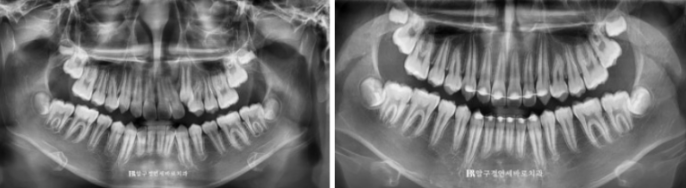

23.03~24.06

치료 전 후 자료입니다.